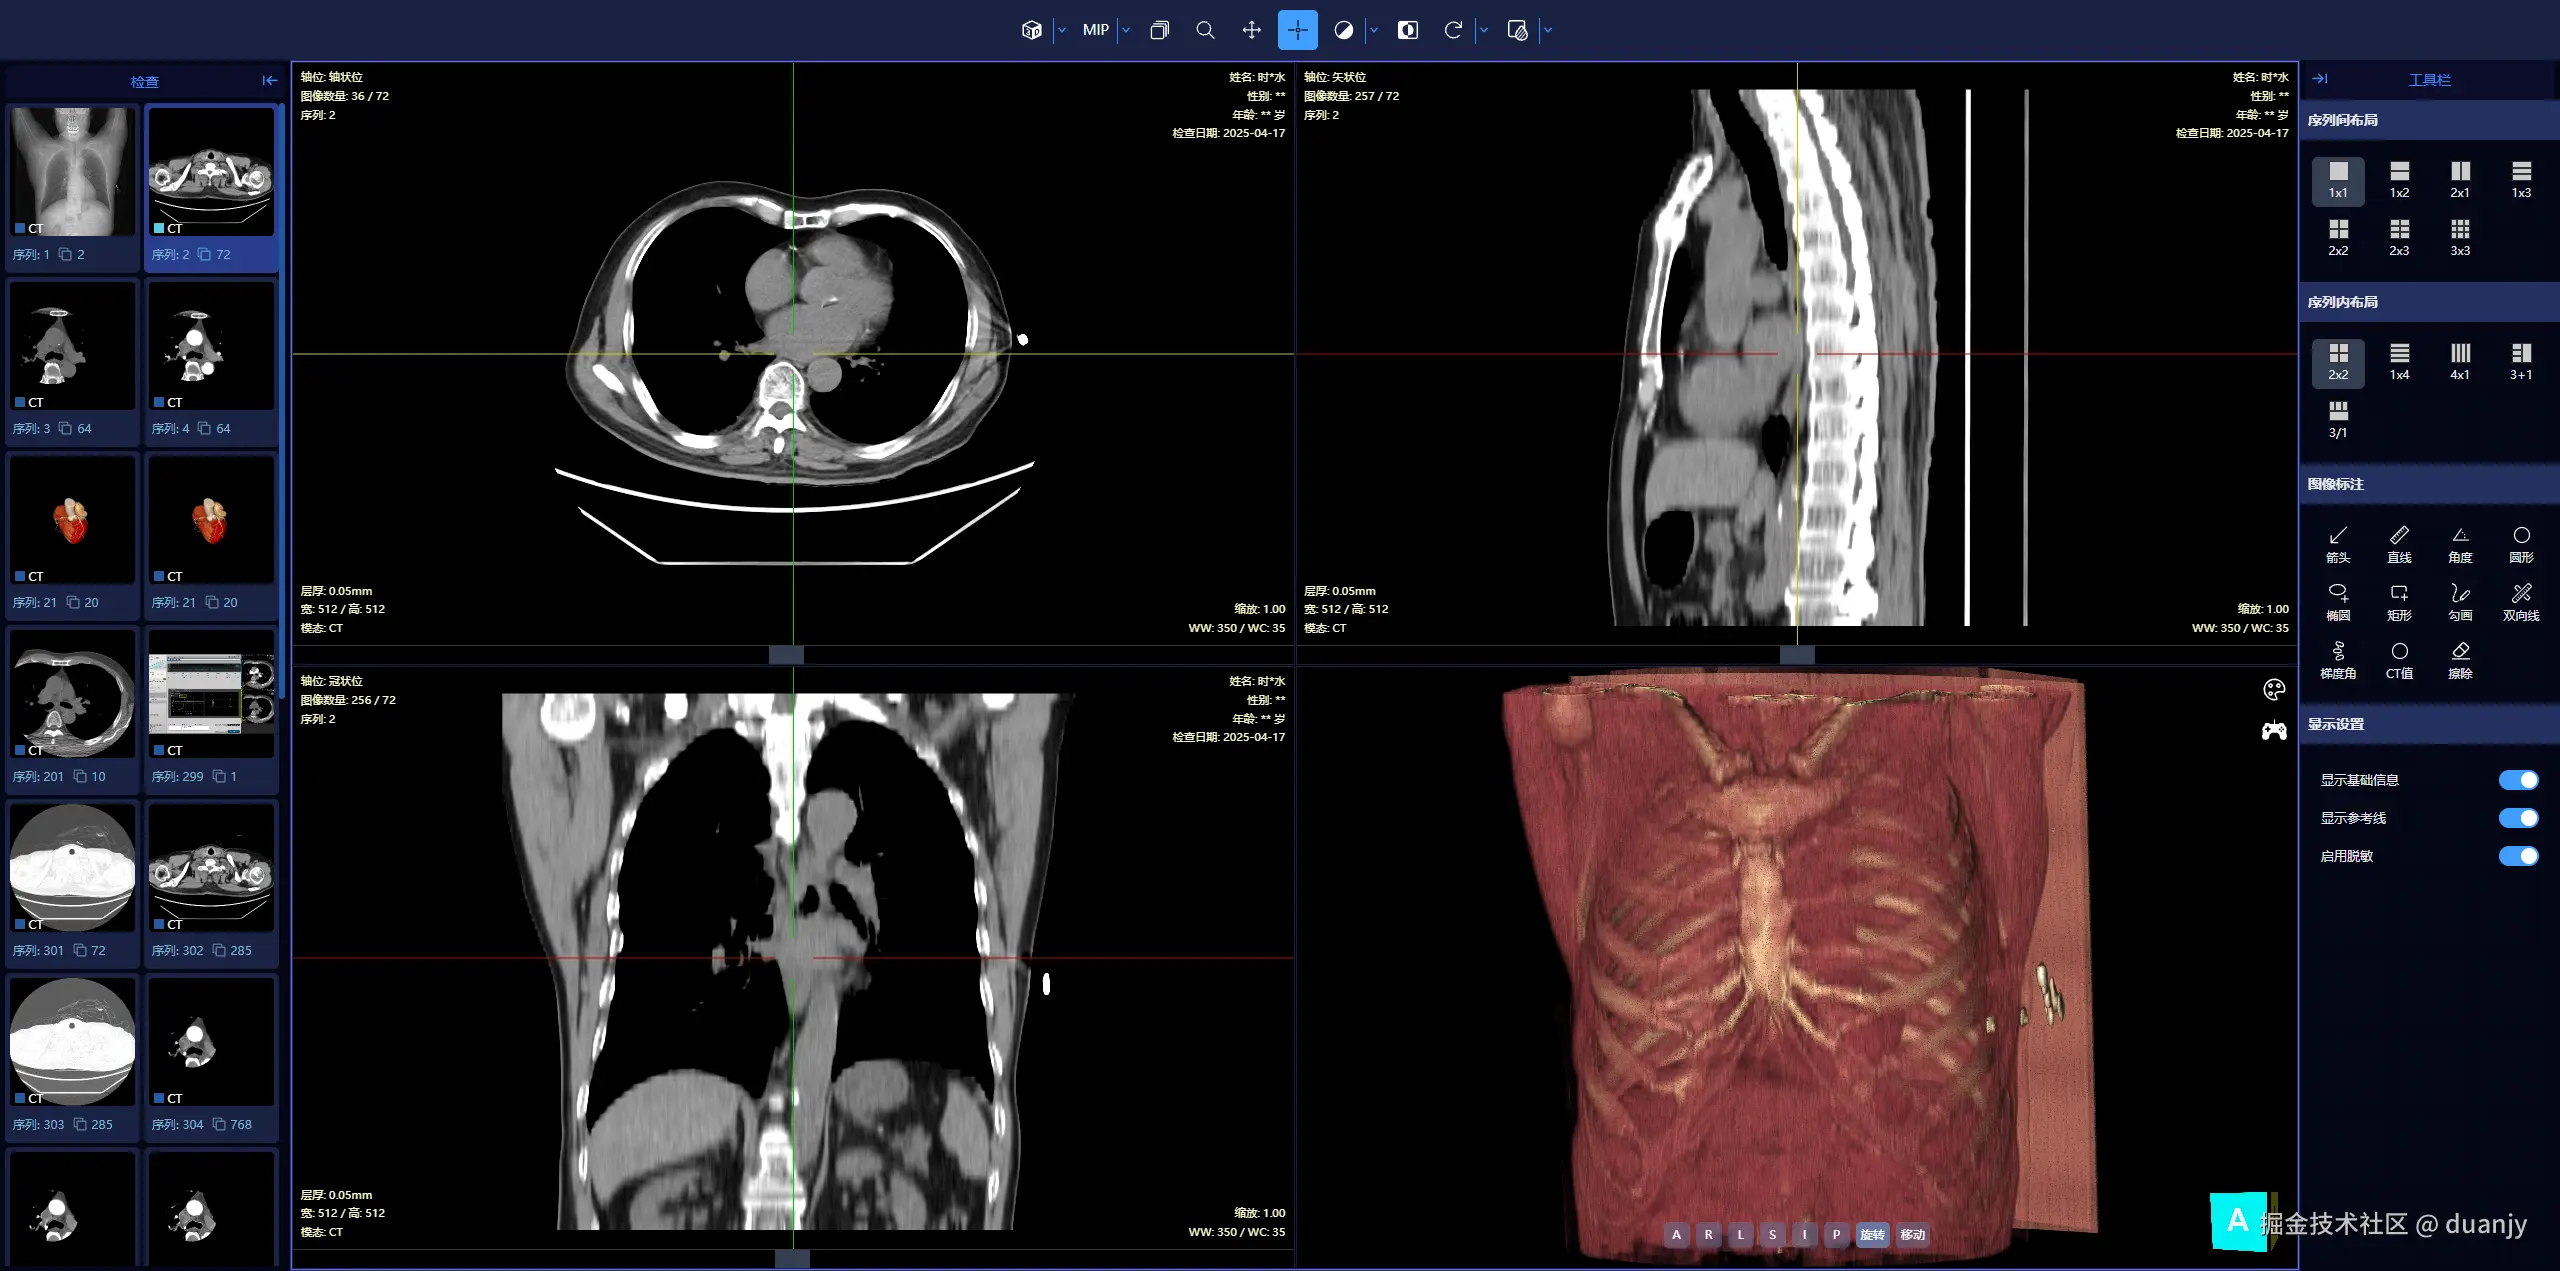

1. PC端 – 三维重建

screenshot-3d.png

支持在 PC 和手机端 打开,可以查看 二维平片三维重建